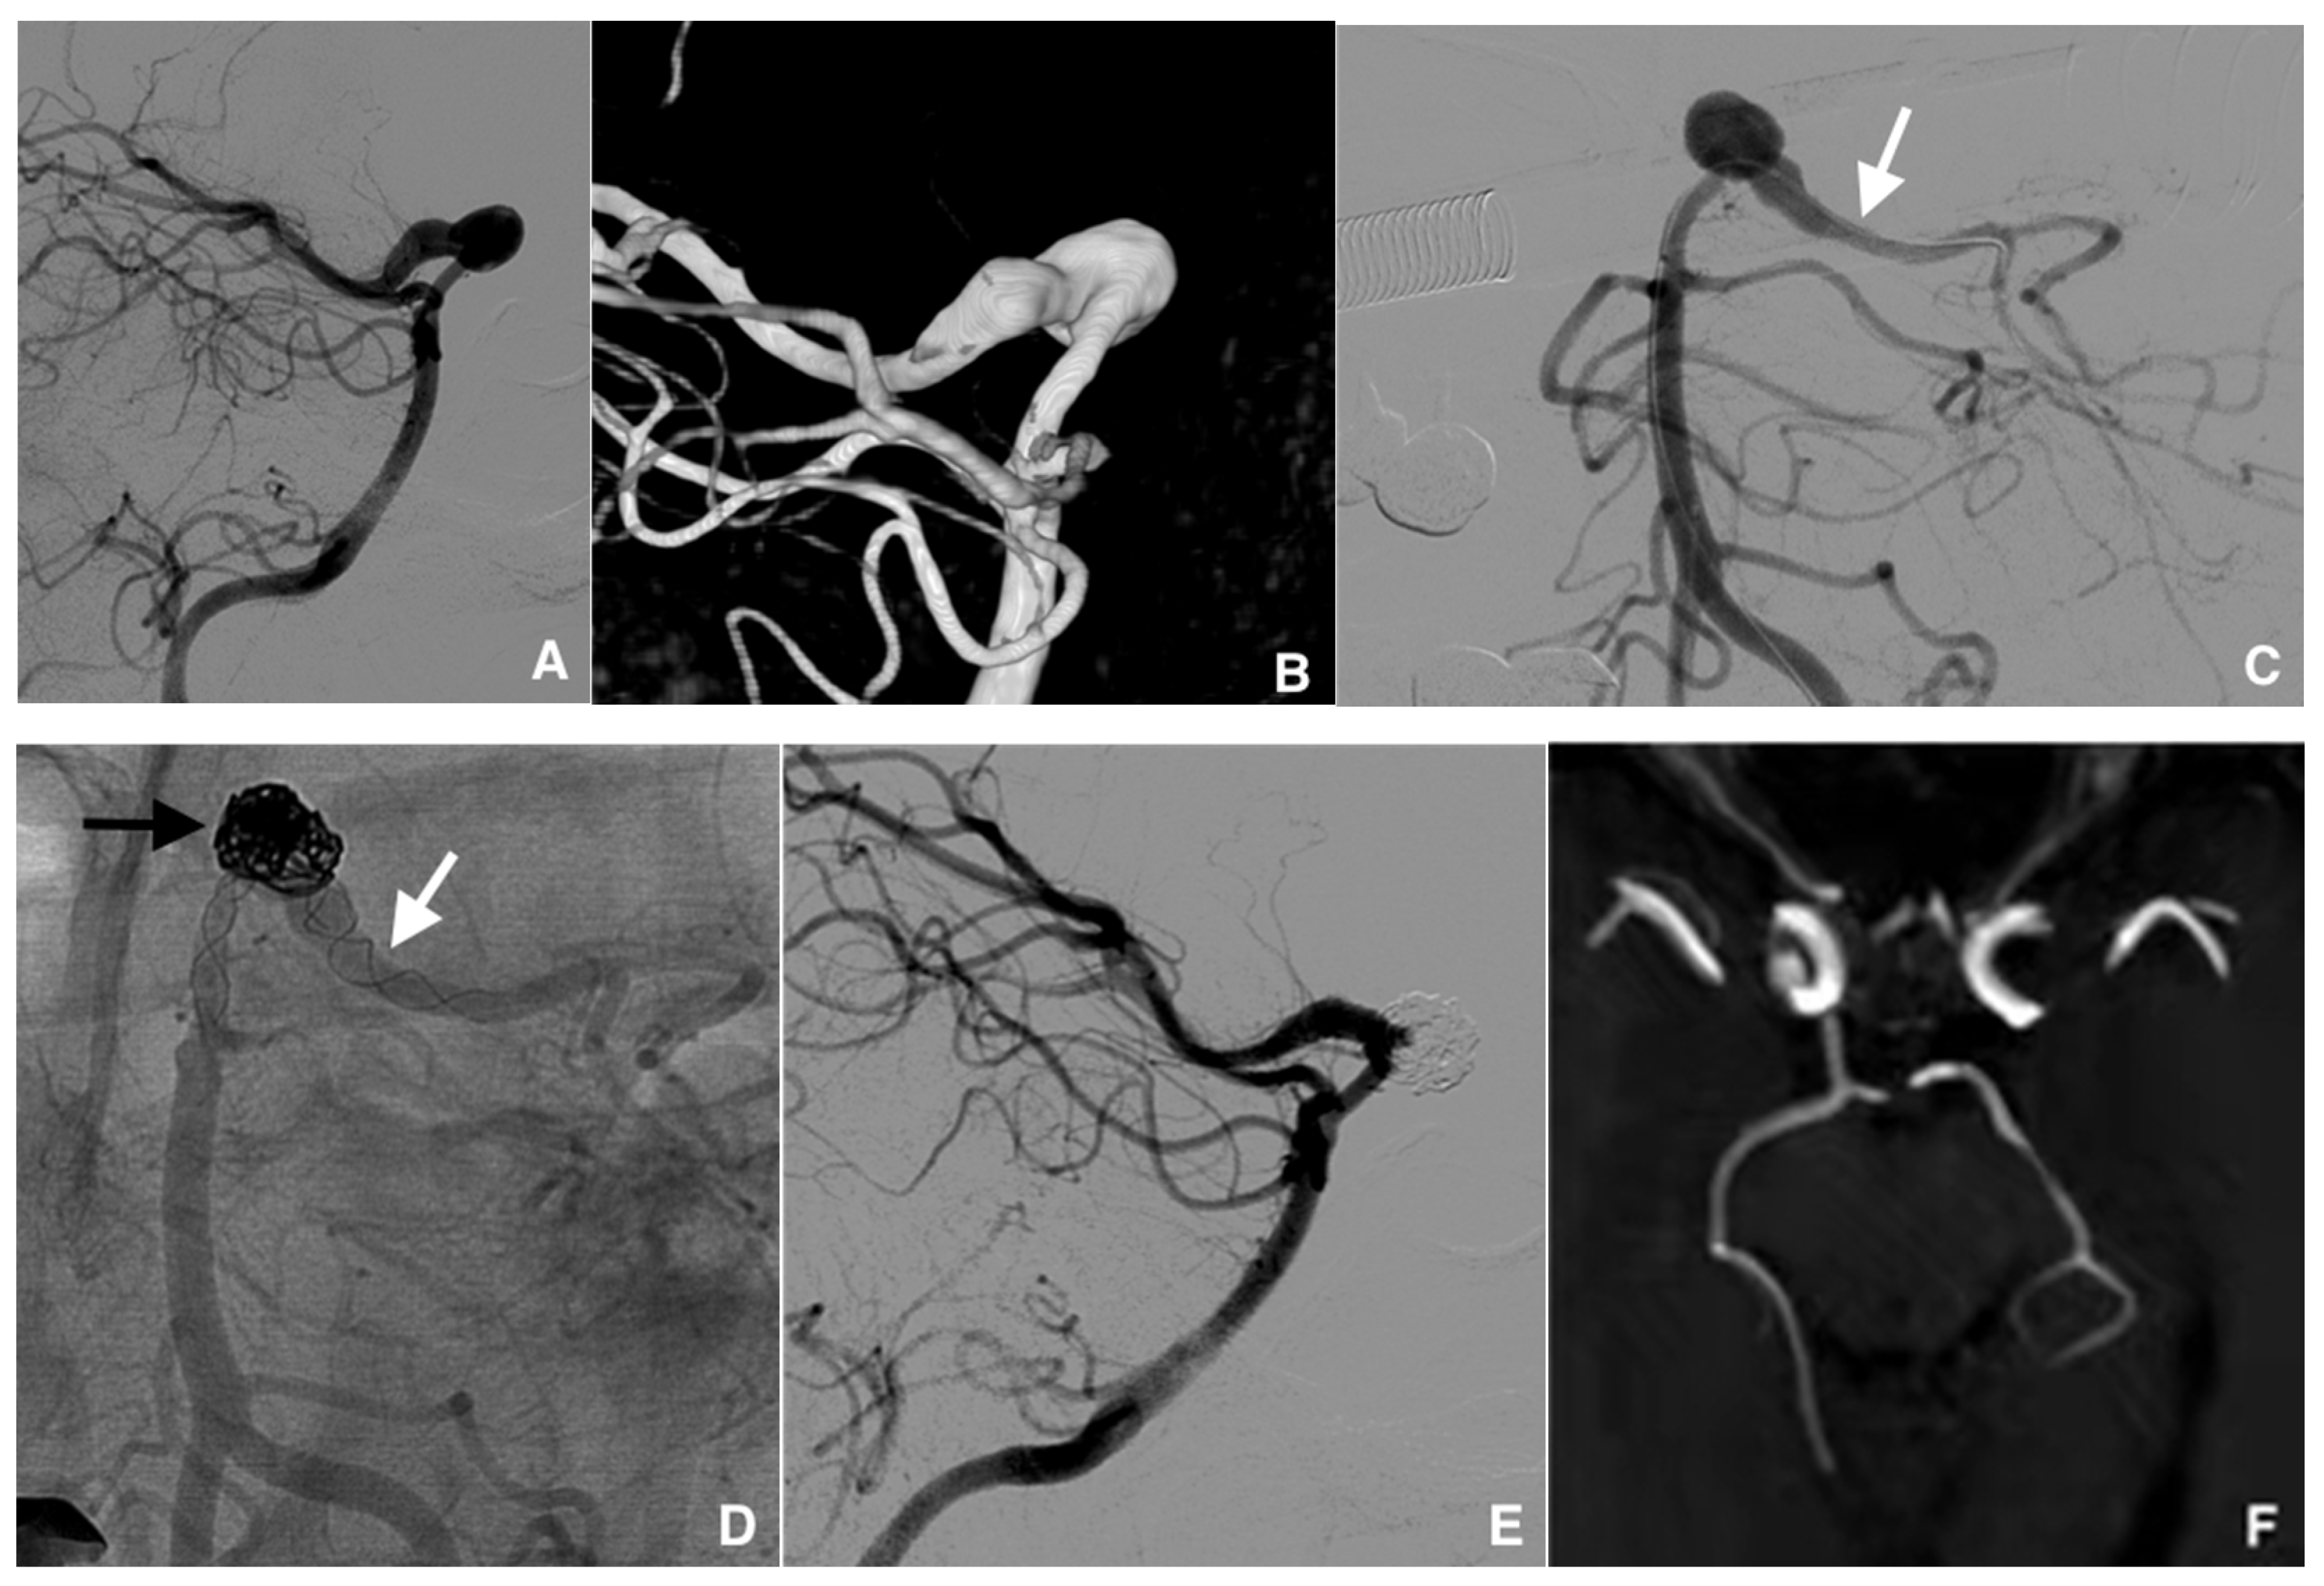

The SAC methods used included the stent-jack technique (n = 18, 27%) (Figure 2), stenting after coiling (n = 14, 21%), coiling through the stent struts (n = 10, 15%), the jailing technique (n = 4, 6%), and rescue stenting (n = 4, 6%). Other methods used were the SWS technique (n = 11, 17%) and T stenting (n = 4, 6%).

Figure 2.

Example of management of a dissecting intracranial aneurysm (IA) (length, 20 mm; wide, 7 mm) in a 52-year-old woman treated with stent-jack technique. (A) Pre-treatment digital subtraction angiography (DSA) of the fusiform IA of the left posterior communicating artery (lateral view). (B) Image reconstruction of the IA with volume rendering technique. (C) Cathetherism of the aneurysm-carrying vessel (white arrow) in a posterior–anterior DSA projection. (D) Nonsubtracted post-treatment control DSA image, posterior-anterior projection, showing the widest part of the IA filled with coils (black arrow) and two Leo stents implanted using the telescopic technique (white arrow). (E) DSA image at the end of the procedure, lateral projection: the IA is partially excluded from the intracranial circulation. (F) Magnetic resonance imaging with 3D time-of-flight view, at 36 months posttreatment control: the IA is completely excluded and the formerly aneurysm-carrying vessel displays regular endoluminal signal.